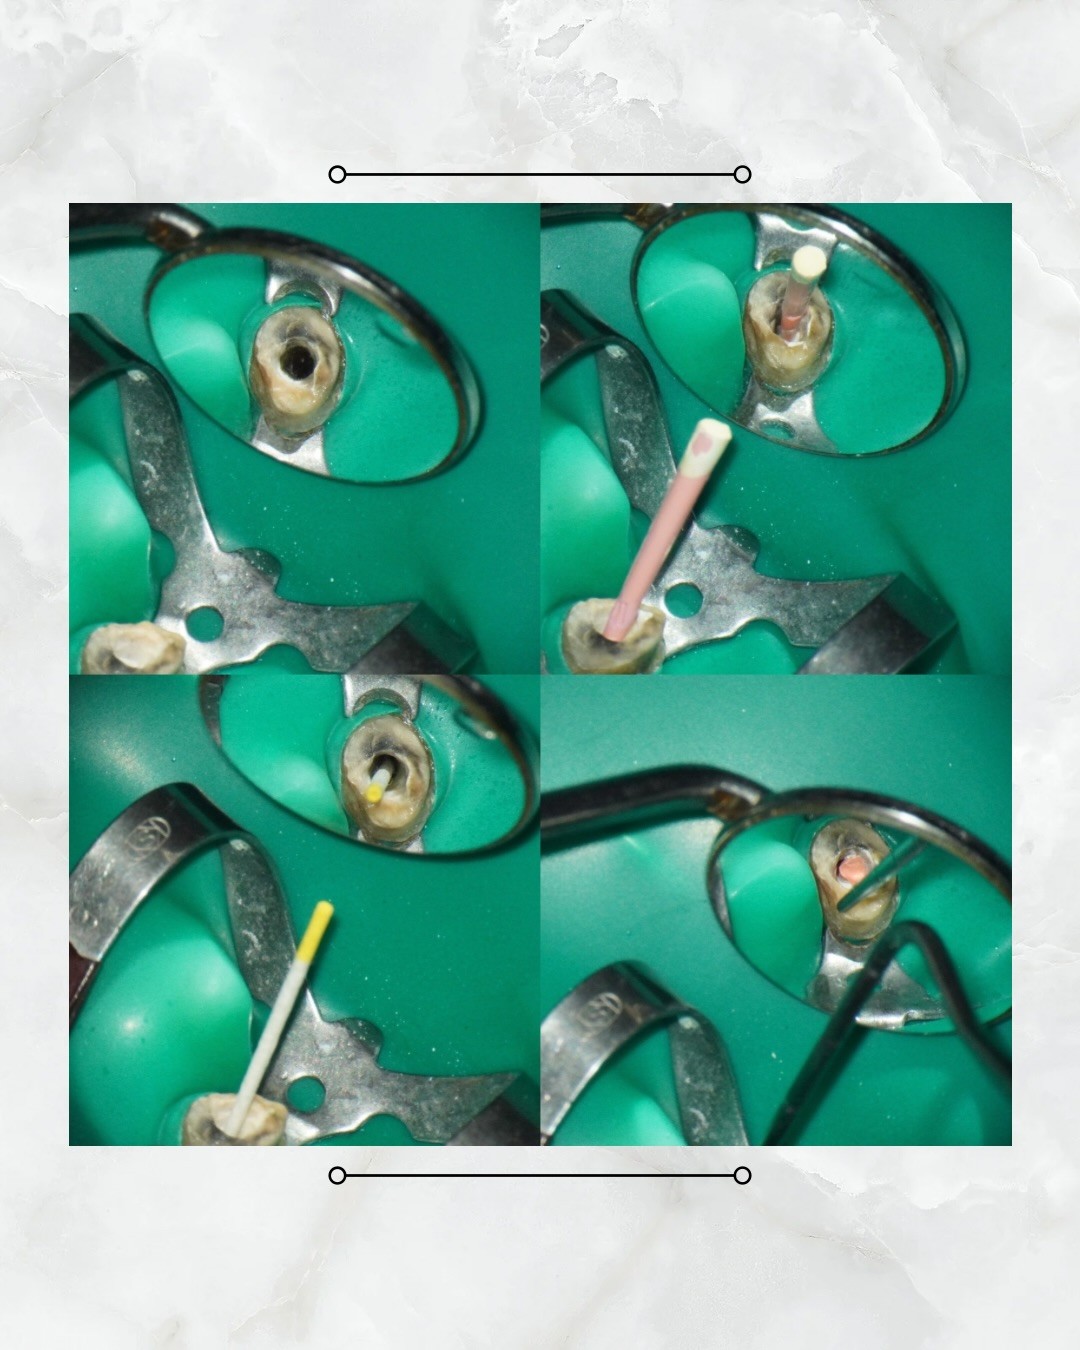

Z老先生於去年底因牙齒斷裂,導致既有牙橋脫落。經評估發現,該牙位殘留牙根過去已接受過根管治療。考量患者後續重建計畫以活動假牙為主,因此需先完善殘根處理,並進行附連體製作,作為活動假牙的前置準備。

本案例治療重點在於進行顯微鏡輔助下的二次根管治療(re-treatment)。治療過程中,需徹底移除既有根管內的填充材料,並重新進行根管充填。臨床上,舊有填充物常因壓實程度高而較為緻密,加上部分患者根管解剖結構彎曲,均可能增加清創與移除的難度。

所幸本案例中,殘根內僅殘留少量牙膠(gutta-percha, GP),在1至2次治療內即順利完成清除,並完成再次根管充填封上。後續即可銜接活動假牙相關重建療程,為患者恢復咀嚼功能與口腔健康🎉